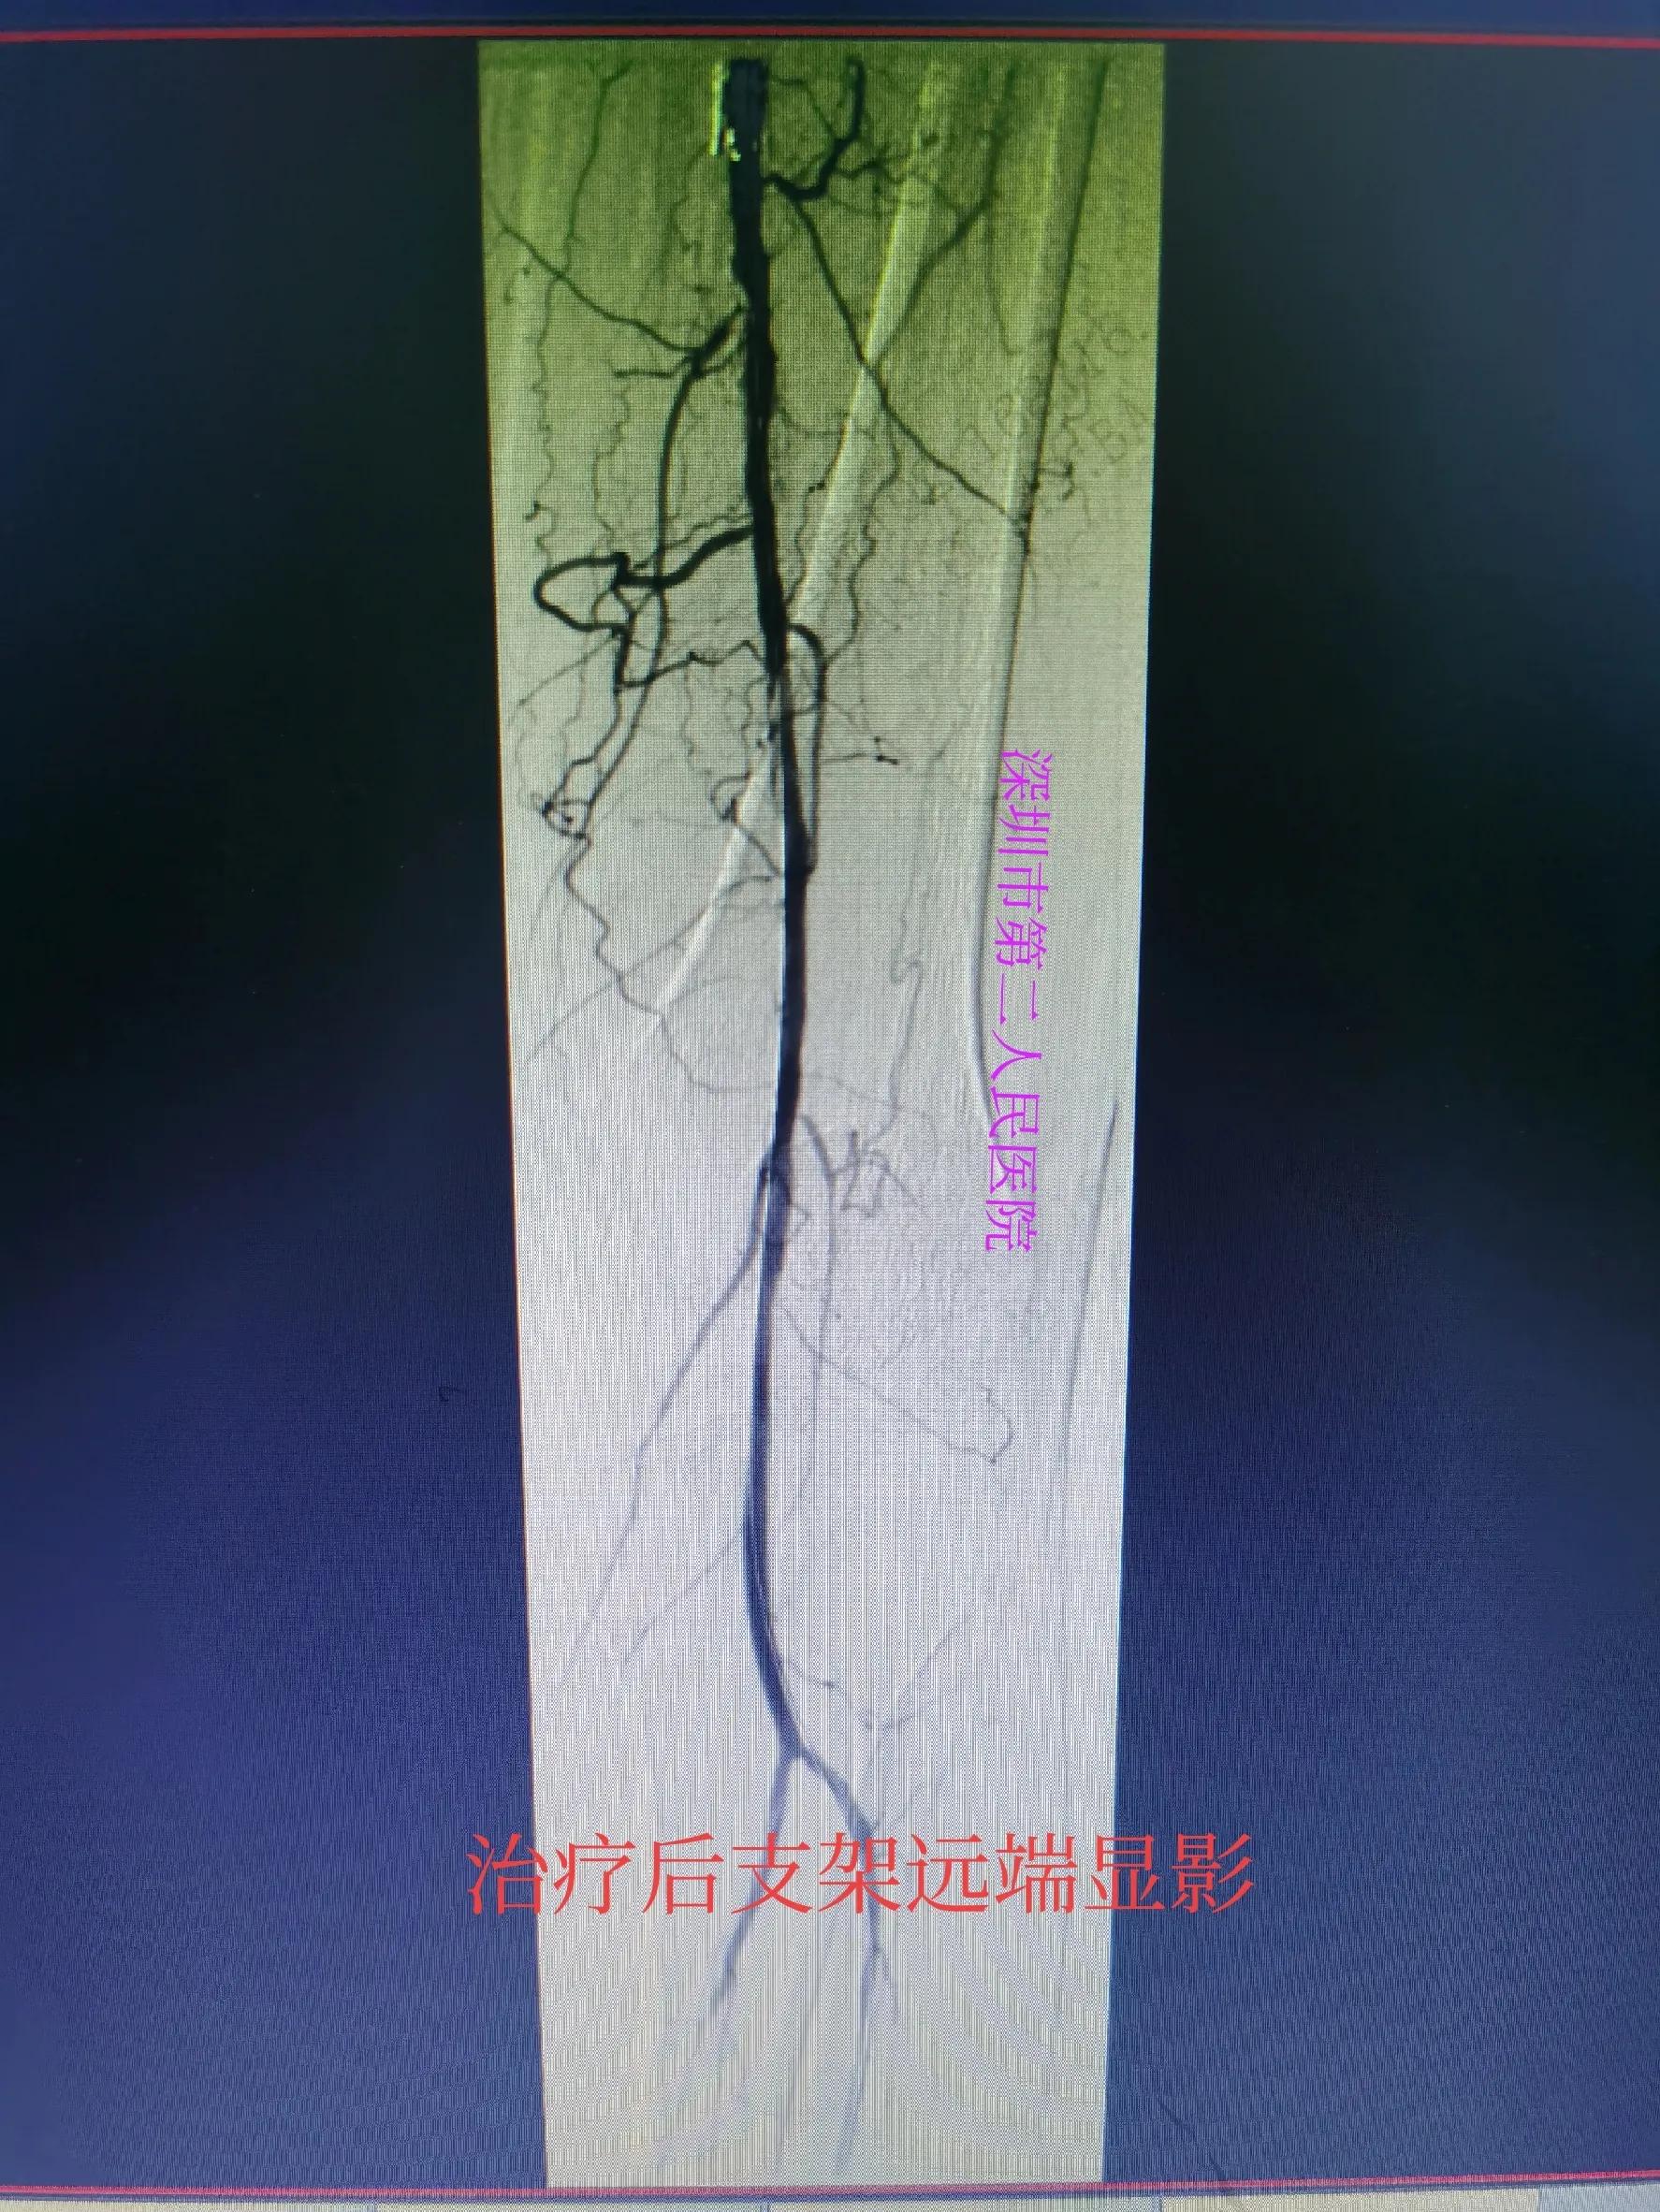

经过三个多小时的积极药物溶血栓、球囊扩张等治疗后,病人左小腿血流恢复,左足背动脉搏动良好。病人疼痛缓解,足部皮温恢复正常,比右腿还好。以下附上术前术后检查对比图。

支架远端显影良好